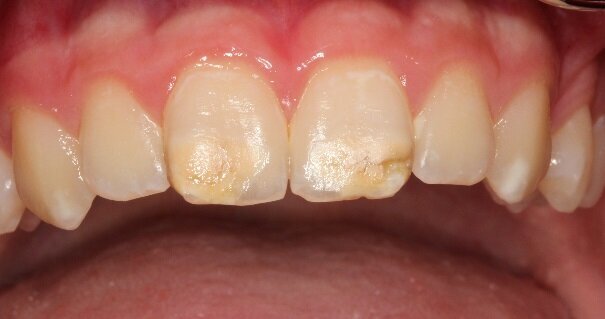

The photograph shows a severe form of MIH. The tooth on the left erupted incompletely developed. The molar was highly sensitive to cold and touch, and brushing was painful, as evident from the surface deposits. The second molar was also affected by the condition. (Photograph: Prof. Norbert Krämer)

With MIH, permanent anterior teeth and, increasingly, second primary molars often present with defective structures. Clinically, the severity may vary greatly, from a single cusp to the entire surface of the tooth. The mild form of MIH appears as white-yellowish or yellow-brown irregular opacities of the occlusal surface or cusps. The severe form exhibits chipped or abraded enamel and dentine of varying degrees. The affected patients suffer from pain when drinking, eating and brushing their teeth.